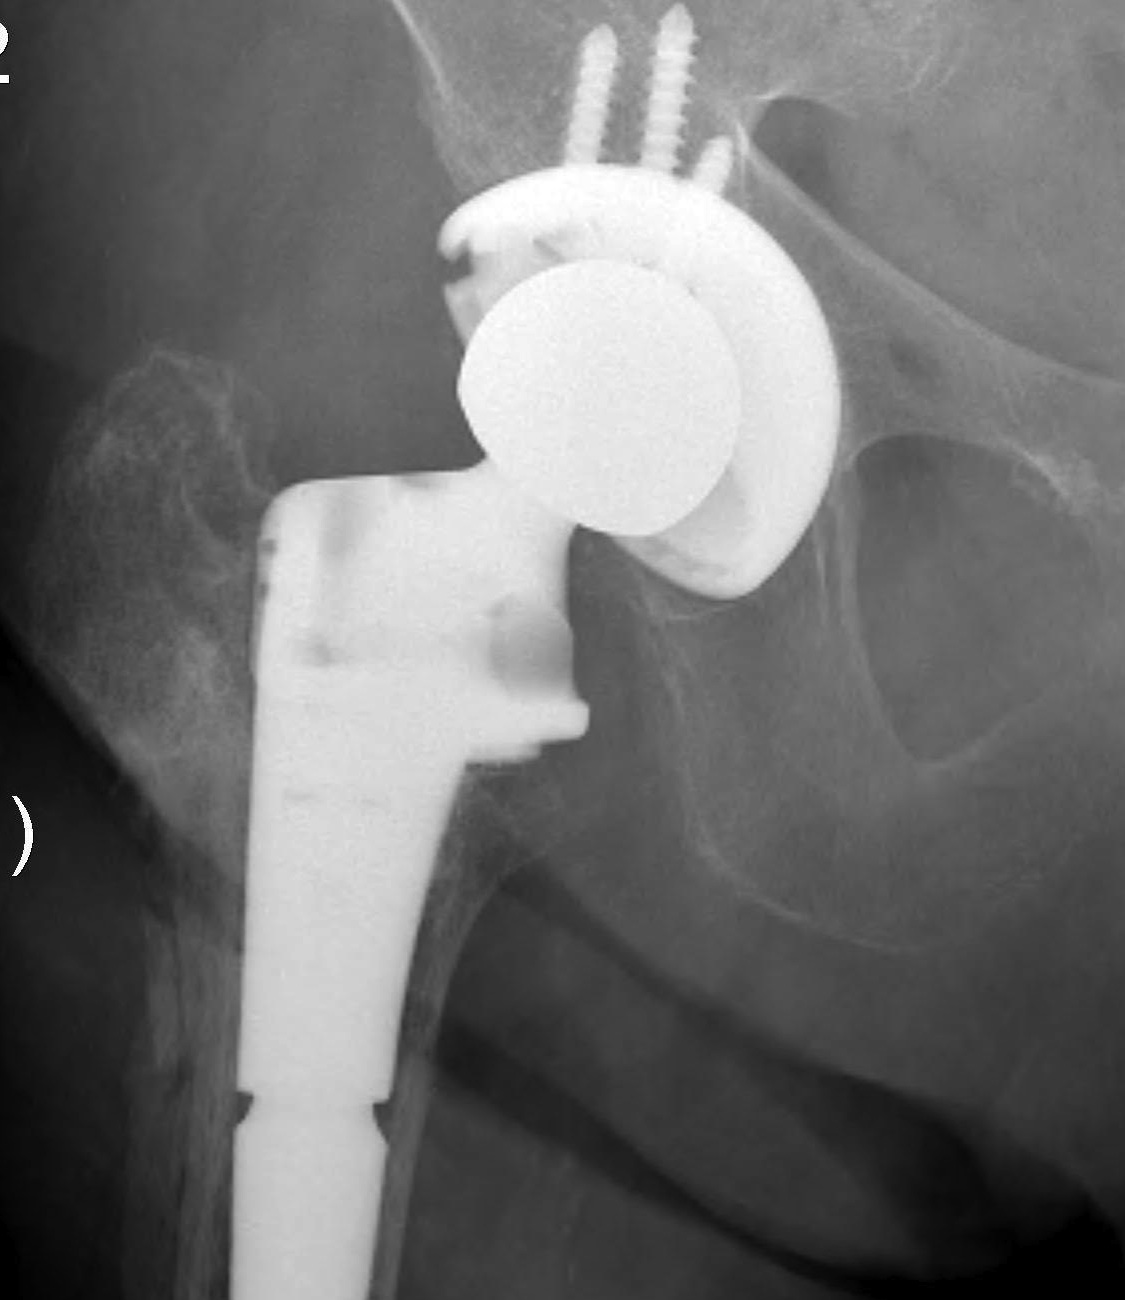

C. Proximal Femoral Replacement / Tumour prosthesis

Results disappointing

- however design may be improving

Malkani JBJS Br 1995

- 33 hips 11 years

- poor function (50% severe limp or unable to walk)

- 64% 12 years survival

- 22% dislocation

D. Bulk Structural Proximal Femoral Allograft

Technique

- desired stem cemented into allograft

- press fit distally into host femur

- step cut graft host junction

- secure cerclage wire and onlay cortical strut

- proximal host bone wrapped around allograft with ABD preservation

- very important – abductor mechanism must be secured and protected